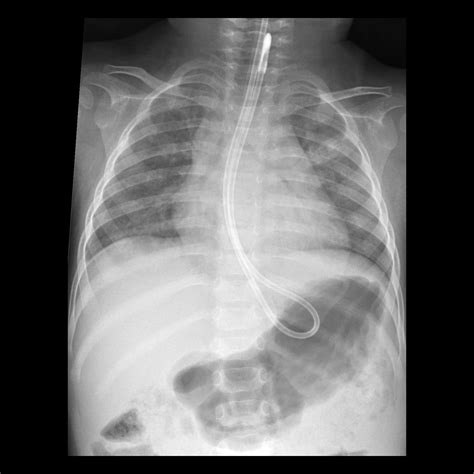

• Radiologically Inserted Gastrostomy (RIG) Tube: This type is inserted using X-ray guidance. It is often used when endoscopic placement is not possible.

5. Verification: The placement of the tube is verified using X-ray or other imaging techniques.